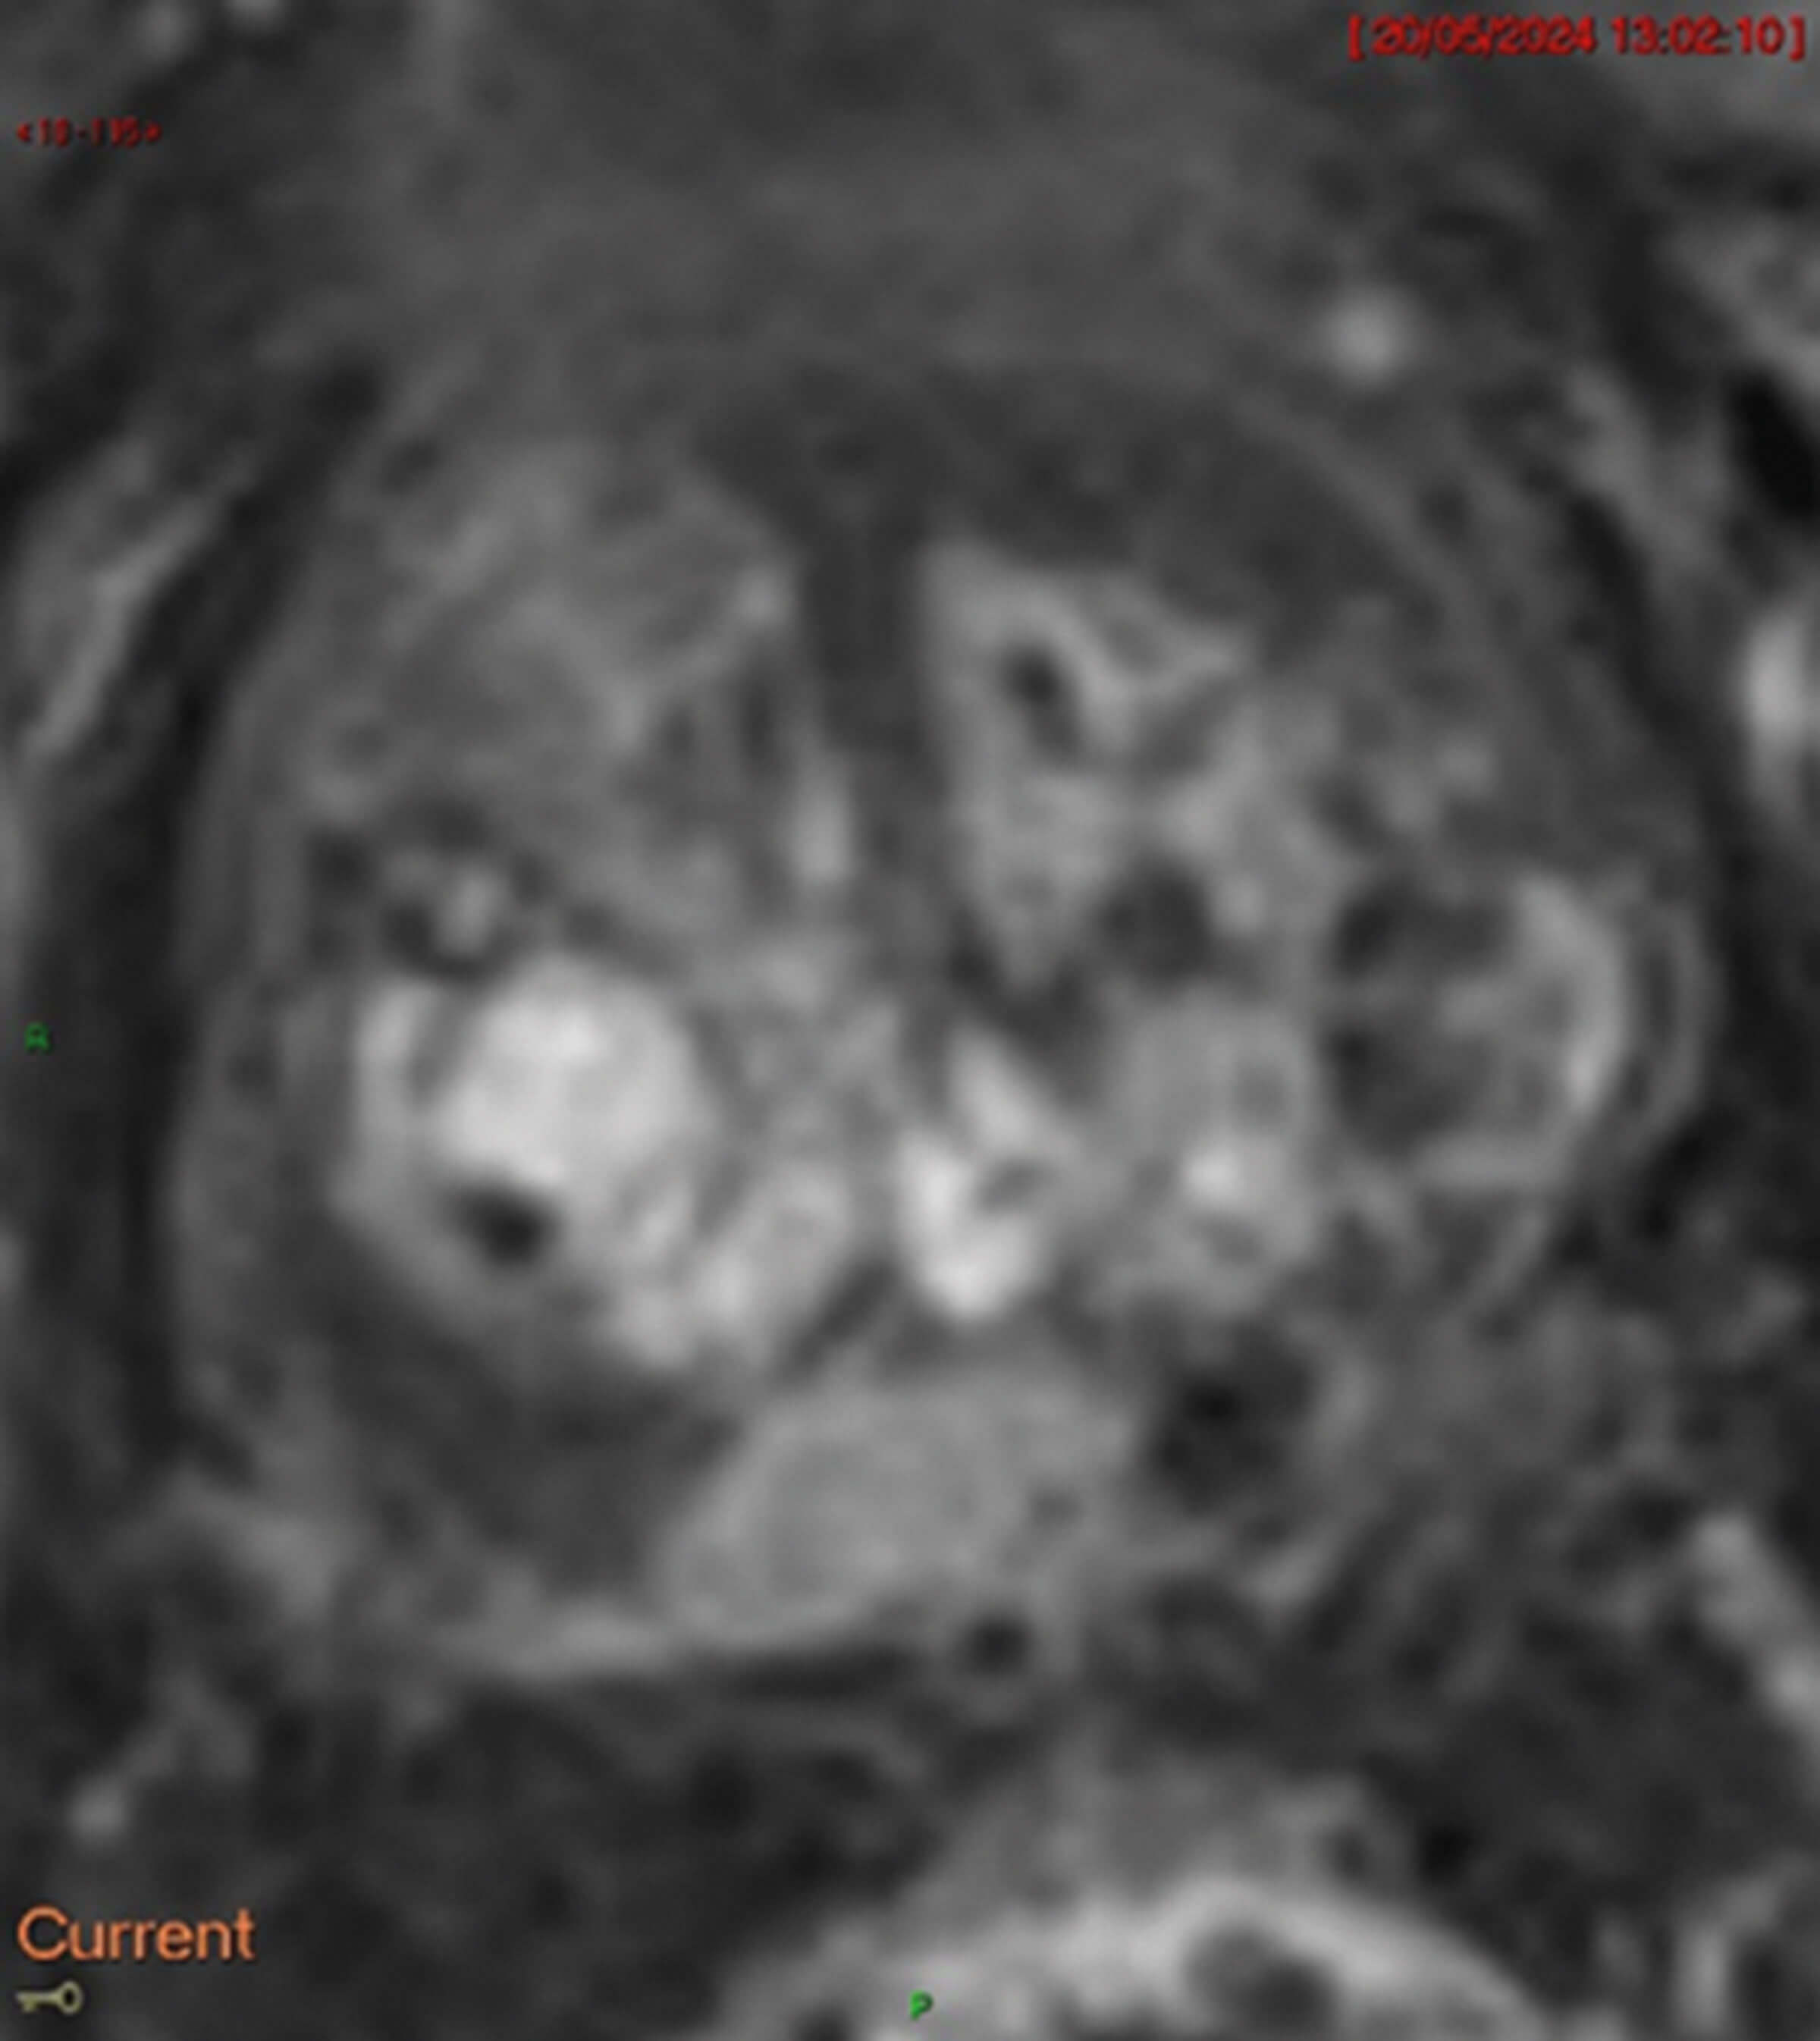

- Figures 2-4 are the different MRI sequences. What sequences are they and what do they represent?

4. Diffusion weighted imaging (DWI, Figure 2) measures how easily water diffuses across cells, with restricted diffusion indicating increased cell density and tumour matrix.

The b-value (s/mm2) is a measure of the different gradients of diffusion weighting applied and by applying different pulses and calculating diffusion gradients aids in tumour detection. Different b-values are required to calculate the apparent diffusion coefficient (ADC, Figure 3), and higher b-values increase sensitivity to restricted diffusion, aiding in tumour detection. ADC is calculated by a specific formula.

Cancer typically appears bright on DWI (Figure 2) and darker on ADC (Figure 3) and radiologists compare sequences to check if they correlate.

Dynamic contrast enhancement (DCE, Figure 4) completes the multi-parametric MRI (mp-MRI) sequence. Without DCE, it is termed bi-parametric MRI (bp-MRI). DCE assesses tissue enhancement after Gadolinium contrast administration, exploiting tumour neoangiogenesis and abnormal vessel leakage which cause contrast stasis in tumour regions and appear as enhancement.